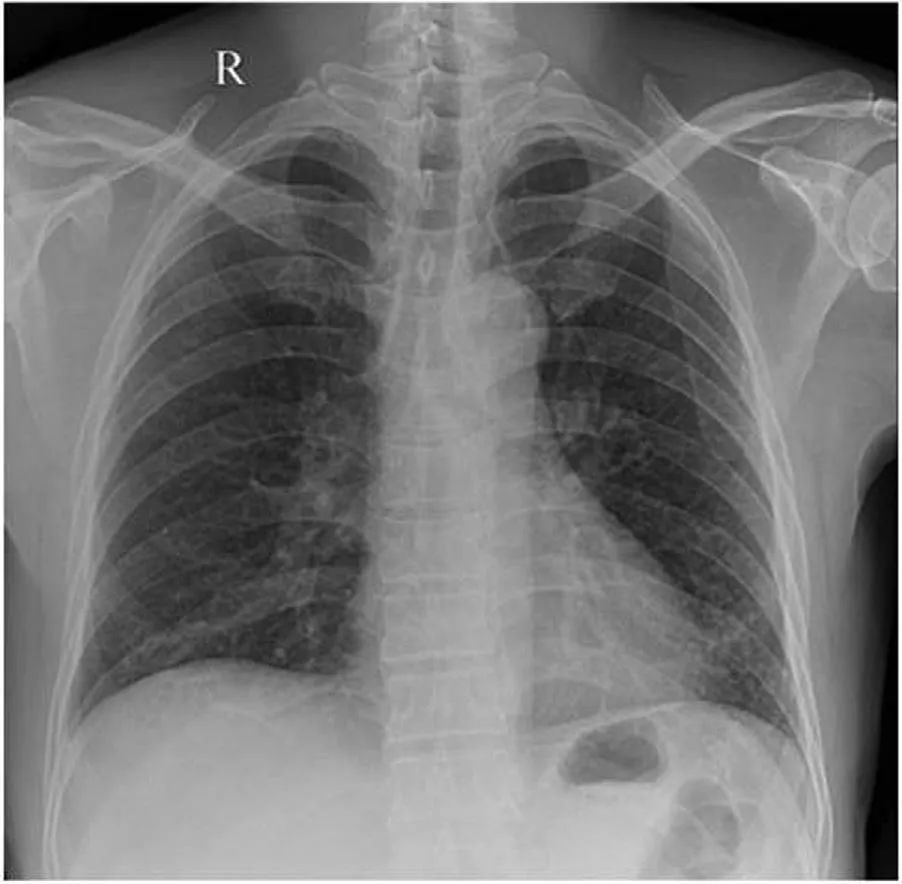

肺炎的胸片

肺炎的胸片,胸片 女性

肺炎的胸片表现图片

肺炎胸片

肺炎胸片详解

肺炎胸片图解

肺炎胸片影像图片

大叶性肺炎胸片

支气管肺炎胸片表现图